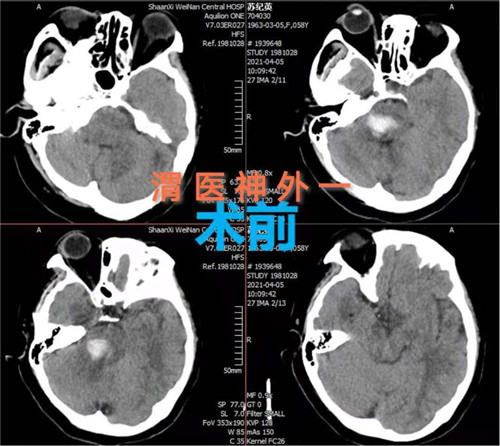

患者女性,58岁,突然意识不清3小时,行头颅CT检查提示:脑干出血。入院时患者深度昏迷,GCS评分6分。患者脑出血部位特殊,病情危重,手术风险大,并且既往有高血压、糖尿病史,围手术期随时有死亡可能。神经外科一病区赵金安主任带领团队评估手术风险,立刻上报医院,并和家属及时沟通,经反复讨论后最后决定实施开颅脑干血肿清除术:一级入路为右侧乙状窦后入路;二级入路为三叉神经下一面听神经上脑桥侧安全区。

手术计划制定后,即刻安排手术,手术麻醉科确定了由麻醉医师钟永慧、配合护师党海婷和马丹组成的麻醉护理团队。手术历时近4个小时,手术过程患者生命体征平稳,术中总出血量约50毫升,术后患者恢复自主呼吸。术后次日患者生命体征平稳,意识恢复,右侧肢体活动正常,左侧肢体活动正在恢复中。